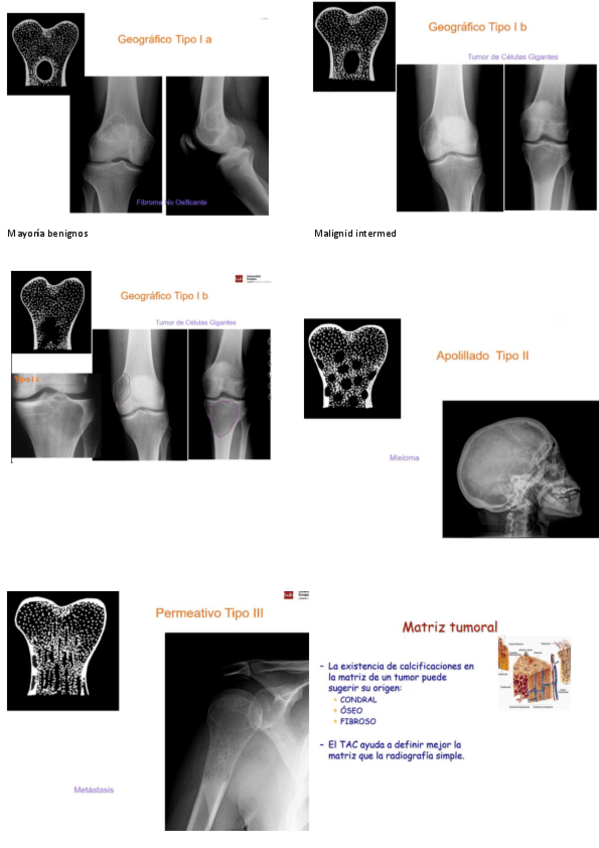

He publicado nuevos apuntes de 3º Anatomía patológica general: Tema-61.-Tumores-oseos-y-lesiones-psuedotumorales.docx